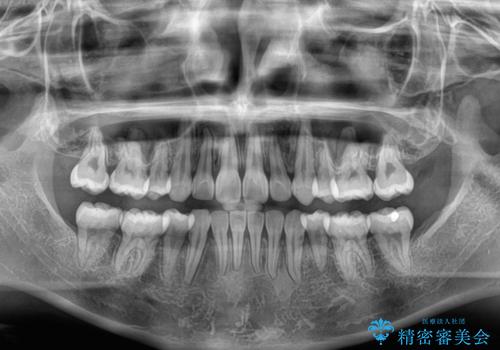

下唇に前歯が当たって跡が残ってしまう状態でしたが、スッキリとした口元に仕上げることができました。